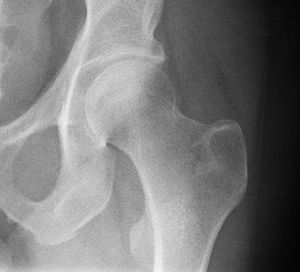

Radiograph of a healthy human hip joint

الردف أو الورك Hip منطقة من الجسم تقع بين الجذع والفخذ. ويتشكل مفصل الردف من عظم الردف الذي يتكون من ثلاثة عظام: عظم الحرقفة وعظم الإسك وعظم العانة، ومقدمة عظم الفخذ. وتتكيف مقدمة عظم الفخذ داخل الحُق، وهو تجويف في عظم الورك. ويشكل هذا النسق مفصلاً كرويًا حُقيًا، مما يعطي متانة كبيرة، ويسمح بمدى واسعٍ من الحركة في جميع الاتجاهات. وتحيط عضلات قوية عديدة بالمفصل، تتضمن العضلة الألوية الطرفية، وتكون عريضة ومستديرة في الخلف، والعضلة الألوية الوسطى في الجنب، والعضلة المستقيمة الفخذية الطويلة الشريطية في المقدمة. وتجعل هذه العضلات المفصل ثابتًا قويًا، بحيث يستطيع المرء أن يقف. وهي أيضًا تنقل الأرجل أثناء المشي والجري.

ويُولد العديد من الأطفال، وتجويفهم الوركي قليل العمق. ويطلق على هذه الحالة خلع الورك الولادي. وفي الأعمار المتقدمة، يُصبح عنق عظم الفخذ الذي يوجد أسفل مقدمة عظم الفخذ مباشرة، ضعيفًا، بحيث يسهل كسره. ويمكن إصلاح الكسر، بتثبيت رأس عظم الفخذ على العنق، بمسمار من الصلب المقاوم للصدأ. ويعاني كثير من ضحايا التهاب المفاصل، من ألم مُعجِز في مفصل الردف. وفي هذه الحالات، يمكن استبداله بحُق بلاستيكي وكرة معدنية بالمفصل.